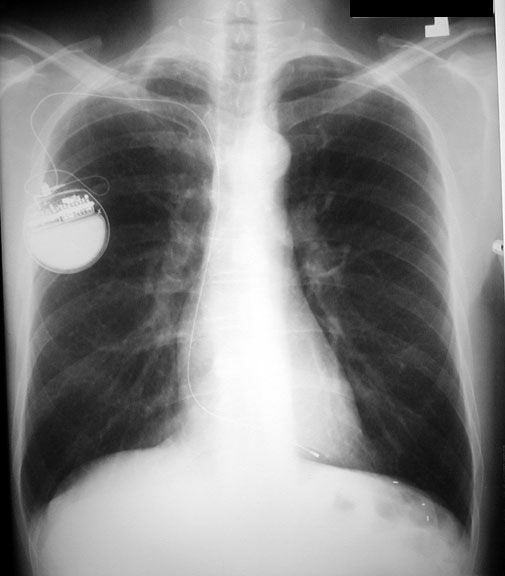

Pacemaker:  Note the path of the catheter from the right side.